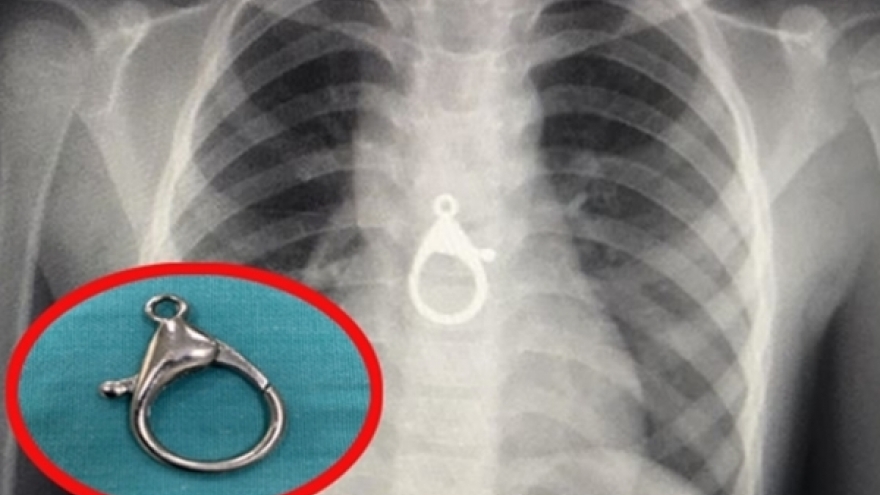

Nuốt phải móc khóa, bé trai 5 tuổi nhập viện cấp cứu

Bác sĩ Nguyễn Thanh Tiên - Trưởng khoa Tai Mũi Họng (Quảng Nam) cho biết, vừa gắp thành công một dị vật ra khỏi thực quản bé trai 5 tuổi.